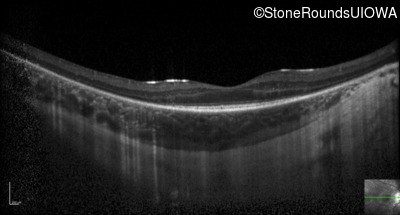

Optical Coherence Tomography - Right - 20/100 -2

Exemplar / OCT Stack